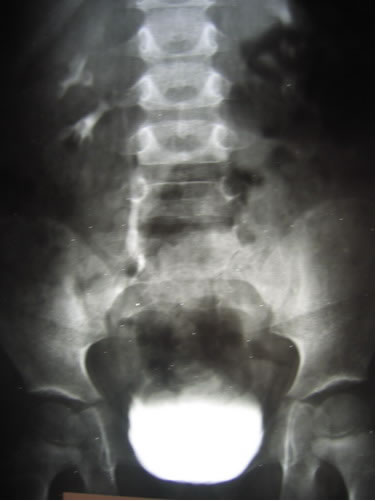

Экскреторная урография

Цистография